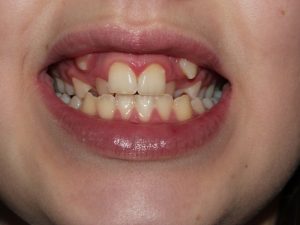

شکل- نیمه نهفته شدن دندان نیش فک بالا (ماگزیلاری)

در صورتی که دندان نیش نهفته یا نیمه نهفته باشد (شکل بالا)، برخلاف دندانهای عقل کشیده نمیشود بلکه برای بیرون زدن آن در موقعیت مناسب در قوس دندانی تلاش میشود.

تکنیکهای مورد استفاده برای کمک به بیرون زدن دندان نهفته در مورد هر دندان نهفته دیگری در قوس دندانی بالا یا پایین قابل انجام هستند اما در بیشتر موارد برای دندان نیش فک بالا استفاده میشوند. ۶۰% از دندانهای نیش نهفته در سمت کام قوس دندان (به سمت سقف دهان) قرار دارند. بقیه دندانهای نیش نهفته در میانه استخوان پشتیبانی کننده قرار دارد و در بالای ریشه دندانهای مجاور یا در سمت فیشیال (چهره ای) قوس دندانی گیر کرده اند (شکل بالا).